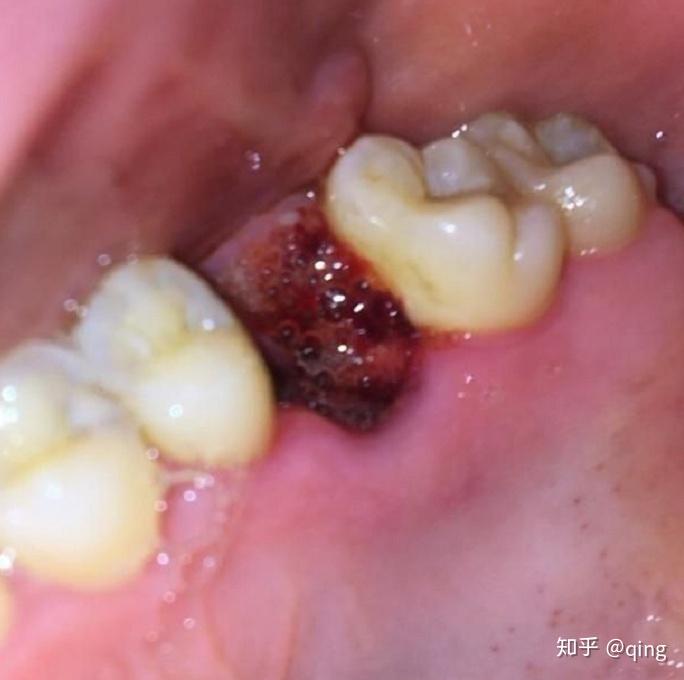

拨过智齿的亲们你们的拨牙窝是怎样长平的